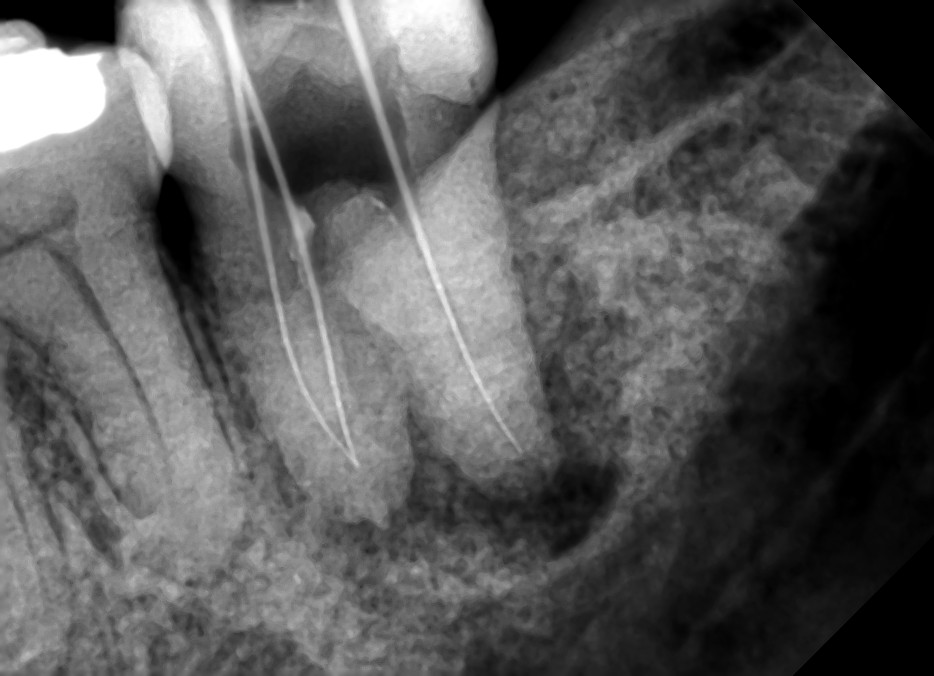

Then pandemic struck, where I probably have only made two visits/adjustments during the whole year of 2020. But even before the start of the lockdown (or after about 17 months of treatment), my teeth and jaw have miraculously aligned in spite of my age. Before starting with the treatment plan, the TMJ specialist told me that there is no guarantee of success (or the desired results may not be achieved) given my age, that they even made me sign a waiver. Though I now understand my body (where I wrote about understanding and listening to your body in my article https://columbusbee.blog/2020/03/28/my-gut-feel-against-the-virus/), I’m still surprised at times on how my body works. Like when I underwent root canal treatment also with the same clinic this year. I have a molar tooth (the tooth at the farthest end) that was decaying and that the infection has already spread both in the gums and the jawline where the x-ray shows loss of bone mass and gum tissue due to infection. Two dentists of the clinic (from different branches) have suggested tooth extraction but after learning what I’ll go thru if I decide to have tooth implant to replace the extracted tooth (denture is no longer an option coz being the farthest tooth, there is only one adjacent tooth to support the same), I decided (and insisted) to save the infected tooth instead thru root canal treatment. Again, miraculously, what seems to be a hopeless case has proven naysayers wrong by just having faith on the body’s healing powers (coupled with mental affirmation that the tooth will be saved). After several bi-weekly visits in a span of 3 months (with the same number of COVID swab test for every visit), the tooth was saved where the infection on the gum tissue started to disappear, the bone mass on the jawline started to regenerate, and what used to be wobbly is now a tooth firmly rooted. My body works in mysterious ways.

(Left) Around the tip of the root of the tooth is a hollow dark spot which is a manifestation of gum tissue infection and loss of bone mass on the jawline. (Right) Three months after the start of the root canal treatment, you see a significant improvement where the dark spot is no longer there which means that the infection is gone and gum tissue and bone mass start to regenerate.